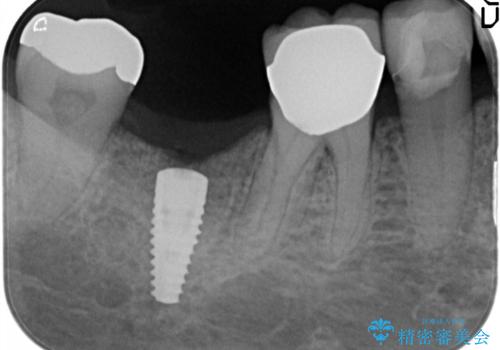

他院で抜歯後いらしたため、骨ができるのを待って、オペは2回法で行っております。

2回法の利点は、骨増成が確実であることと、FGGが可能で長期に安定した歯ぐきが得られることです。